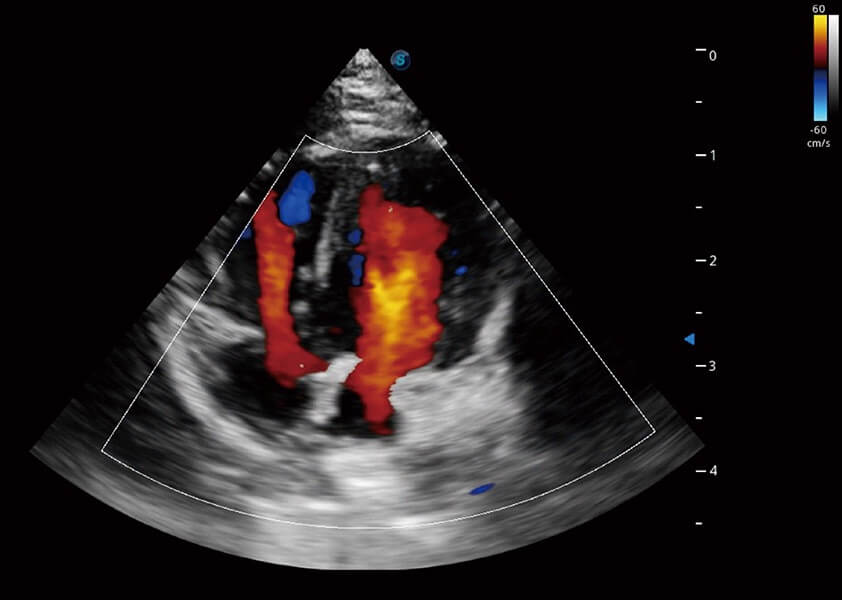

优异的基础图像

(犬)四腔心血流

• TDI 组织多普勒成像

实时用颜色表示心肌组织运动,观察和定量组织的运动情况,对快速检测与评估心肌的灌注和活性、电传导及心肌收缩和舒张功能等均能提供重要的诊断信息。

(犬)心脏组织多普勒